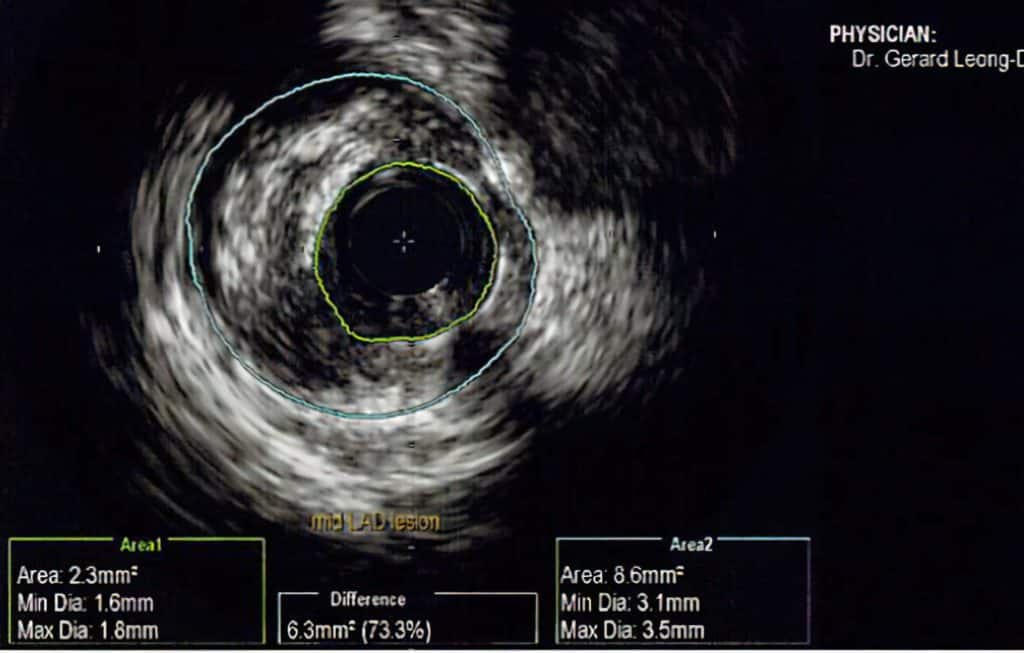

Modalitas tambahan yang dapat digunakan untuk menilai arteri koroner lebih lanjut

Cadangan Aliran Pecahan (FFR)

This is used to assess the degree of pressure-flow difference after and before the stenotic part of the coronary artery.

A fine flexible catheter with a pressure-measuring sensor is threaded through the blockage and pressure readings are taken.